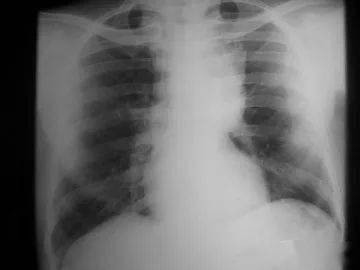

胸腺癌的治療,要根據(jù)TNM的分期來(lái)選擇。術(shù)后治療的選擇,要有明確的病理證實(shí)是R0、R1或R2手術(shù),如果是R1手術(shù),美國(guó)NCCN指南(2012 Version2)推薦術(shù)后放療+化療,R2手術(shù)也如此。關(guān)于是否照射心包,要根據(jù)術(shù)前的CT,看是否有心包受累來(lái)決定。心包的耐受量,三維適形放療(DT45-50GY)應(yīng)該沒(méi)有問(wèn)題,如果長(zhǎng)期生存的年輕者,全心臟的受量要限制在30GY以內(nèi),另外要選擇非蒽環(huán)類的藥物。放療后要補(bǔ)2-3個(gè)療程的化療。